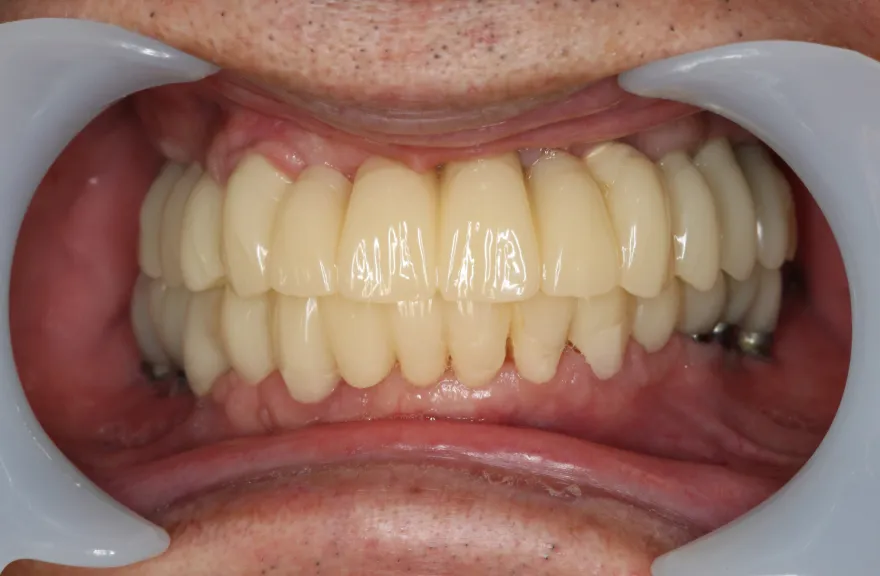

今回で完全に治療をやり切ってしまい、今後は最小限の介入で歯科と付き合えるよう、上下顎残っている歯の全ての抜歯、必要な本数のインプラント埋入、上顎は総義歯形態で対応することとしました。 - 治療のリスク

インプラント治療は決して虫歯にはなりませんしかし歯周病にはなります。

そういった方がインプラント周囲炎になる状況はあまり考えにくく定期的なメンテナンスのみしっかり行っておけば今後の人生においてトラブルを起こすことは心配しなくて良いかと考えます。

上顎の総義歯は時間と共にすり減り、劣化していきます。

10年ごと程度でやりかえが必要な可能性がありますが、虫歯治療のようにお口の中でドリルを使って削ったりする必要はなく、歯型をとって技工士へ製作を依頼するだけなので、治療の負担は限りなく小さいと言えるでしょう。